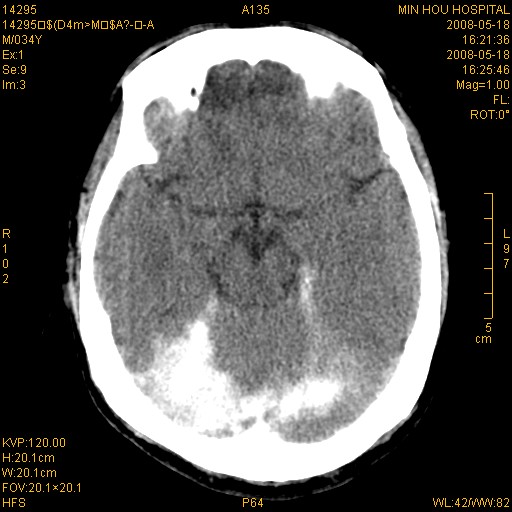

标题: CT13617:双顶叶白质水肿伴大脑镰小脑幕广泛钙化 [打印本页]

标题: CT13617:双顶叶白质水肿伴大脑镰小脑幕广泛钙化

多年前频发抽搐生活不能自理,行ct平扫,诊断为双顶叶占位。因贫未能进一步检查。

目前偶有抽搐,能从事油漆工作。原片未能获取。

双侧侧脑室后脚旁对称性低密度影,符合肾上腺白质营养不良(成人型)改变    小脑幕及大脑廉钙化  可考虑为生理性

支持:1、肾上腺白质营养不良.2、小脑幕、大脑镰广泛钙化。3、建议进一步检查。

硬脑膜钙化是主因,双侧顶叶白质密度减低是可能由于静脉路回流受阻所致。